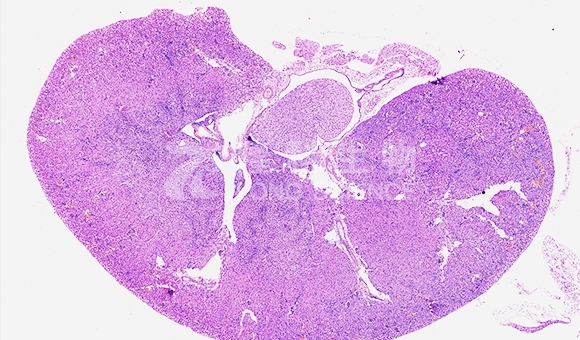

HE染色是一种常用的组织学染色技术,用于观察和分析组织切片中的细胞核、细胞质和胞外基质等部分。HE染色的名称来源于所使用的两种染色剂:血红素(Hematoxylin)和伊红(Eosin)。

HE染色的原理是通过血红素和伊红与组织中的不同成分结合,使它们呈现出不同的颜色。血红素是一种天然染色剂,它与细胞核中的DNA结合,使细胞核呈现出深蓝色或紫色。伊红是一种酸性染料,它与细胞质和胞外基质中的碱性成分结合,使其呈现出粉红色或红色。

完成上述步骤后,HE染色的组织切片可以在显微镜下观察和分析,细胞核呈现深蓝色或紫色,细胞质和胞外基质呈现粉红色或红色,从而提供了组织的整体结构信息。